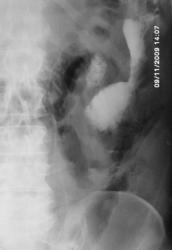

помогите разобраться имеется ли свищ толстой кишки

Как представляекся - оперативное вмешательство на желудке? Сейчас контрастной вещество в основном контрастировало развитую систему свищевых ходов в левом поддиафрагмаальном пространстве. Считаю, что сообщение с просветом поперечной ободочной кишки есть, но основная масса контрастного вещества располагается рядом с нисходящей кишкой. Доказательств  сообщения ходов с протоками панкреас не видно, но она в таких ситуациях принимает участие очень часто... Попытался бы применять встречное контрастирование - все повторить совместно с ирригоскопией, но гарантии в таких случаях не даст никто. Ищи - свищи....

Оперативное вмешательство  в октябре 2009г по поводу гемангиомы левой доли печени в объме резекции левой доли печени и хвоста поджелудочной железы, дренирование поддиафрагмального пространства. Сброса воздуха по дренажу никогда не отмечала.